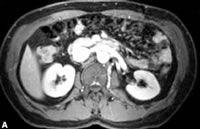

2.影像學檢查

一般只需做B型超聲檢查,以除外結石、腎結核、腎囊性疾病等。某些特殊情況下,可能需做放射性核素腎圖、靜脈腎盂造影、腎臟CT和磁共振(MRI)檢查等。腎圖檢查對急、慢性腎衰的鑑別診斷有幫助。如腎圖結果表現為雙腎血管段、分泌段、排泄功能均很差,則一般提示有CRF存在;如腎圖表現為雙腎血管段較好,排泄功能很差,呈“梗阻型”(拋物線狀),則一般提示可能有急性腎衰竭存在。